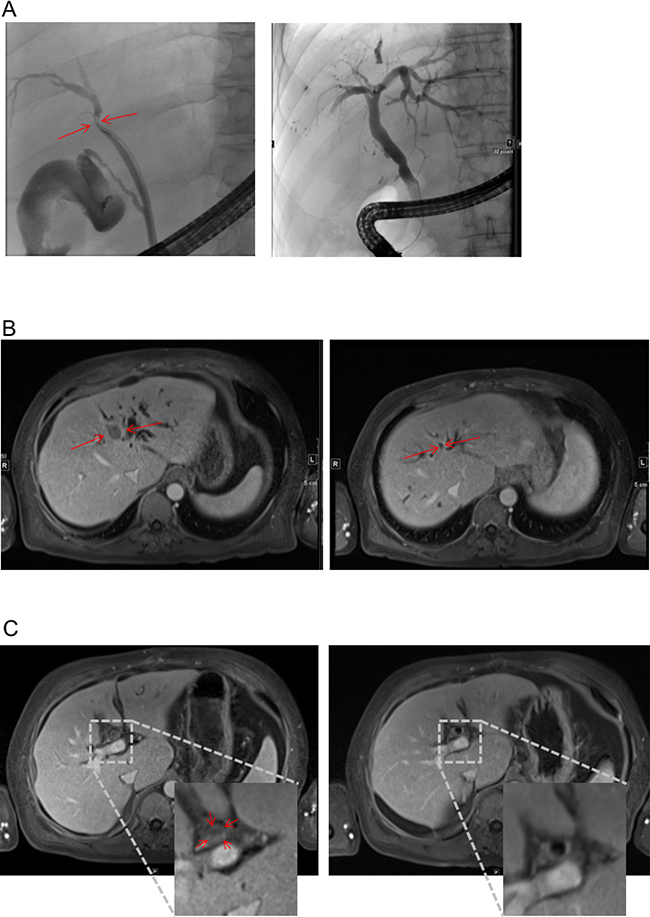

Figure 1: Response to therapy in MRI and ERC. (A) ERC before placement of endoprothesis (left) and after successful therapy (right). Red Arrow heads indicate index lesion and relevant stenosis respectively. (B and C) MRI scan before (left) and after (right) 6 cycles of treatment according to FOLFOX6 regime. T1-weighted, Enlarged inset shows intraluminal tumor in the bile duct (C left).

Bilirubin was elevated to 38 mg/dl (Figure 2). Endoscopic retrograde cholangiography (ERC) showed an unaffected major duodenal papilla. Further examination of the biliary tree revealed a stenosis of the common hepatic duct and left hepatic duct with possible affection of the right hepatic duct, consistent with Bismuth-Corlette type IIIb/IV Klatskin-tumor (Figure 1A). Two plastic stents were implanted in the right and left hepatic duct. Subsequently, bilirubin dropped to 11.4 mg/dl (Figure 2).

Due to its inoperability, undifferentiated histology, and high proliferation rate, it was decided by an interdisciplinary tumor board to treat the patient with chemotherapy. Since bilirubin was still elevated, the FOLFOX6 protocol (fluorouracil 400 mg/m² IV bolus, followed by 46-hour 5-FU infusion [2400 mg/m²], leucovorin [400 mg/m²], and oxaliplatin [100 mg/m²]) that can also be administered in patients with hyperbilirubinemia was chosen [9]. The initial dose was reduced (50%), and therapy was well tolerated by the patient. The patient’s bilirubin dropped into normal range, and a second cycle was given at full intended dose. Therapy according to the FOLFOX6 protocol was administered for 3 months (Figure 2). During therapy, AFP concentration dropped to 12.8 IU/ml and CA 19-9 level to 7.4 U/ml within 24 weeks. MRI-scan showed a marked shrinkage of the intrahepatic tumor mass, dilatation of prestenotic bile ducts was relieved (Figure 1B and 1C). Lymph nodes at the portal vein, the liver hilus and the mesentery remained enlarged, and there was some ascites. 16 months after start of chemotherapy, the biliary plastic stents were removed since the biliary stenoses had disappeared.